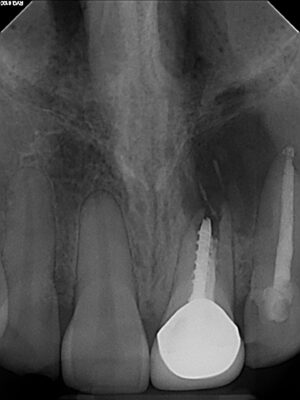

• We all can agree you want a minimum of 1.5 between implant and tooth. What are the risks if it is 1.2 or 1.0. Are they ways to still have success?

Attached is a picture of an immediate implant placement after extraction, threading the needle. In the picture we had 1.5 mm but I know posts with pictures do better lol.